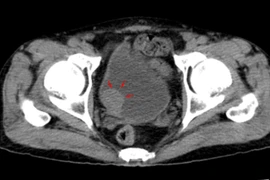

Ung thư bàng quang là bệnh lý đứng thứ hai sau ung thư tiền liệt tuyến thuộc hệ tiết niệu sinh dục và thứ 4 trong các loại ung thư phổ biến. Siêu âm là phương pháp dễ dàng nhìn được hình ảnh khối u, rẻ tiền, không xâm lấn.